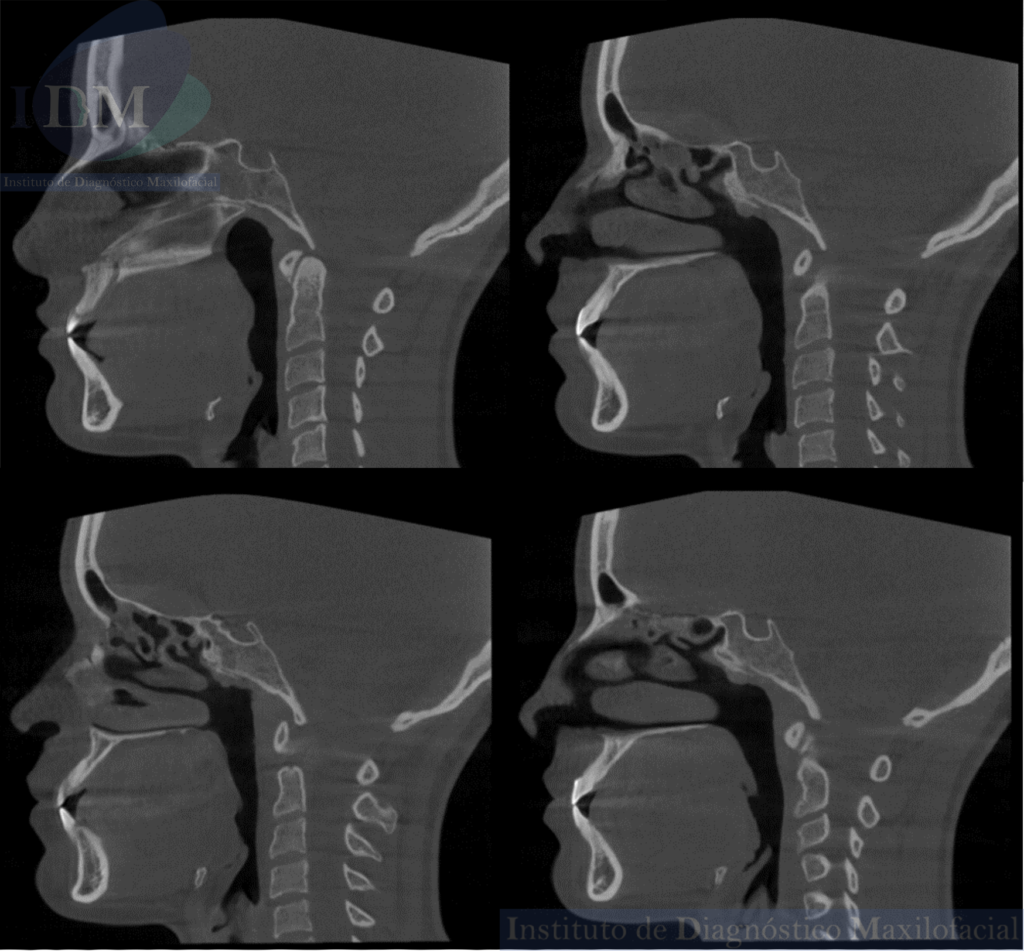

Así mismo en la tomografía volumétrica de haz cónico se evidencia un leve engrosamiento de la mucosa antral de senos paranasales. Siendo lo mas relevante la ausencia de seno esfenoidal en base de cráneo.

CORTES TANGENCIALES